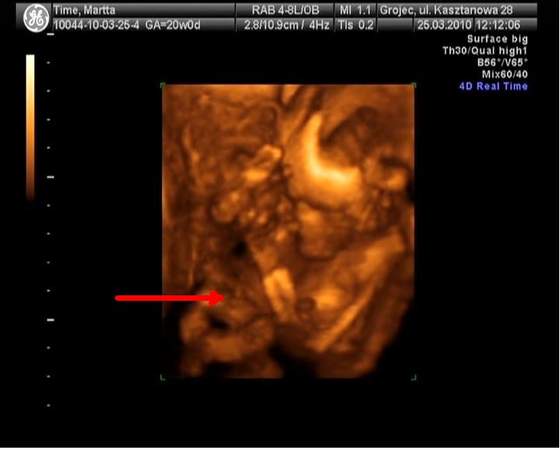

Na tym zdjęciu mój Maluszek trzyma się za nóżki obiema rączkami, widać wypiętą dupkę i taką czarną plamę, a nad tą plamą... strzałka wskazuje o co mi chodzi

Jak sądzicie, czy to może być PTAK????!!!!